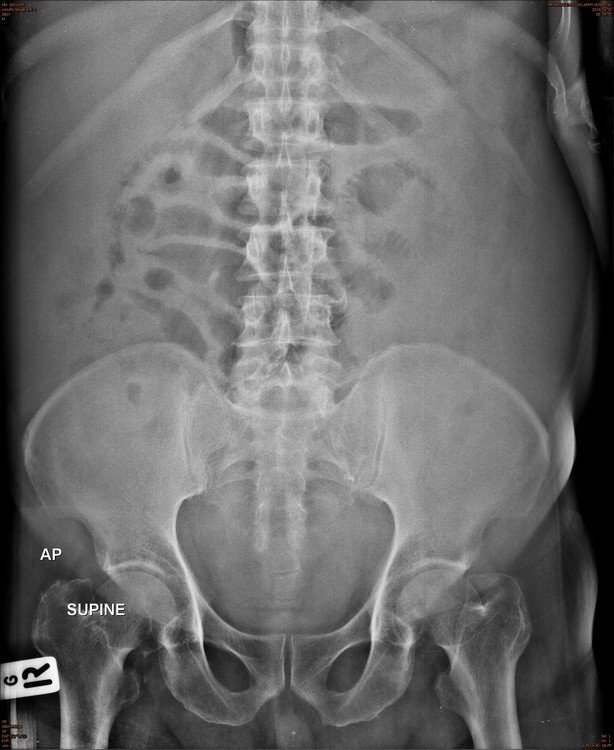

Abdomen : Case 4

History :  A 71-year-old male with abdominal distension

C. Ascites

* Abdominal X-rays should not be used to check for ascites.

* If this diagnosis is suspected then again ultrasound is the best initial investigation, and can also be used to assist drainage.

* Fluid and soft tissues have similar densities, and so ascites may be mistaken for organomegaly.

• In the presence of ascites gas within bowel is located centrally

* Detection of intraperitoneal fluid on plain film requires at least 500 ml

* Plain film findings of ascites include:

• Diffusely increased density of the abdomen

• Poor definition of the the soft tissue shadows, such as the psoas muscles, liver and spleen

• Medial displacement of bowel and solid viscera (away from properitoneal fat stripe)

• Bulging of the flanks

• Increased separation of small bowel loops